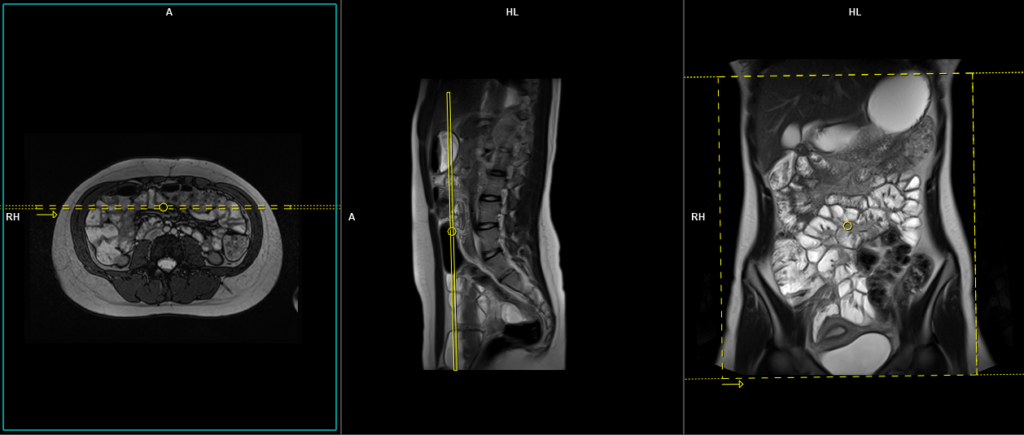

T2 TRUEFISP axial

Plan the axial slices on the coronal image, position the block horizontally across the abdomen as shown, and ensure that the positioning block is also checked in the other two planes. Establish an appropriate angle horizontally across the abdomen in the sagittal plane. The slices must be sufficient to cover the entire abdomen and pelvis from the stomach to the pubic symphysis. Phase oversampling can be used to avoid wrap-around artifacts. Instruct the patient to hold their breath during image acquisition.

The axial scan is performed as two separate blocks with a 20-30% slice overlap between them. The scan is performed this way to avoid any RF inhomogeneity-related artifacts by conducting the scans at the isocenter of the magnet. Use the composing function in the scanner to stitch the two blocks together.

Protocol Parameters TRUEFISP axial

TR 4-5 | TE 2-3 | FLIP 60 | NEX 1 | SLICE 4 MM | MATRIX 320×256 | FOV 350-400 | PHASE A>P | OVERSAMPLE 50% | IPAT ON |